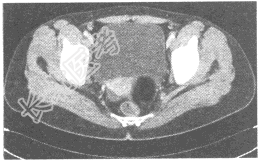

- 单项选择题女,35岁, 下腹部胀痛,CT扫描如图所示, 盆腔内囊实性肿块影,其内CT值不均, CT值-120~360HU不等,最可能的诊断是

A、子宫肌瘤

B、卵巢癌

C、卵巢畸胎瘤

D、卵巢囊肿

E、以上都不是